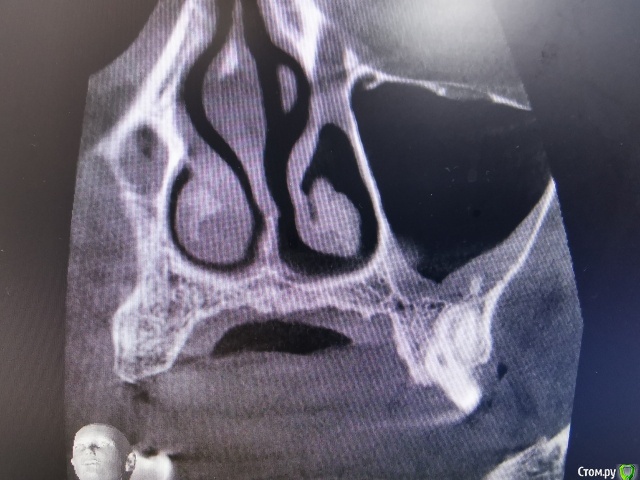

olga.maverick Опубликовано 1 марта, 2021 Поделиться Опубликовано 1 марта, 2021 (изменено) Здравствуйте!Вместо удалённого год назад зуба, 18 февраля врач установил мне в верхнюю челюсть имплант Импро, без синус лифтинга, сказал, что между слизистой и имплантом проложил губку, она рассосётся и кость нарастёт. Он сделал контрольный снимок-рентген, подтвердил, что имплант в пазухе, но под слизистой и это по его мнению норма. Пять дней я пила Амоксиклав по его назначению. Сегодня, первого марта сделала снимок КЛКТ, т.к. не проходит. насморк и дискомфорт в районе пазух.Получилась вот такая картина-сильный отёк в районе правой пазухи , до установки импланта отёка не было, есть снимок, сделанный перед операцией. Помогите пожалуйста разобраться:1) Всё идёт по плану, отёк временная реакция, имплант установлен профессионально или всё плохо?2)Нормально ли, что имплант стоит не посередине, а впритык к одному зубу? Изменено 1 марта, 2021 пользователем olga.maverick Ссылка на комментарий

olga.maverick Опубликовано 2 марта, 2021 Автор Поделиться Опубликовано 2 марта, 2021 Реакция слизистой, после таких операций может иметь место, тем более что ранее имелись проблемы, от решения которых Вы отказались. Все остальные вопросы корректно задать, специалисту который эту работу делал, он в курсе всех нюансов. Таким образом, сохраните хорошие отношения с врачом и свои нервы.Спасибо, разумеется я к нему схожу, как запись подойдет, но жить с имплантом мне, а не врачу, поэтому я не устраняюсь от ответственности и тоже хочу понимать, надо оно мне или нет. В пазухе, где установили имплант, ранее проблем со слизистой не было. В другой пазухе я не отказалась от решения проблемы, ищу пути, врачи ставят противоречивые диагнозы. Кроме того, отёк в пазухе, где стоит имплант, как минимум в два раза больше, чем в другой, больной пазухе и с ним я жить не намерена. Сколько времени должно пройти после имплантации, чтобы отёк спал, если это временная реакция? Ссылка на комментарий